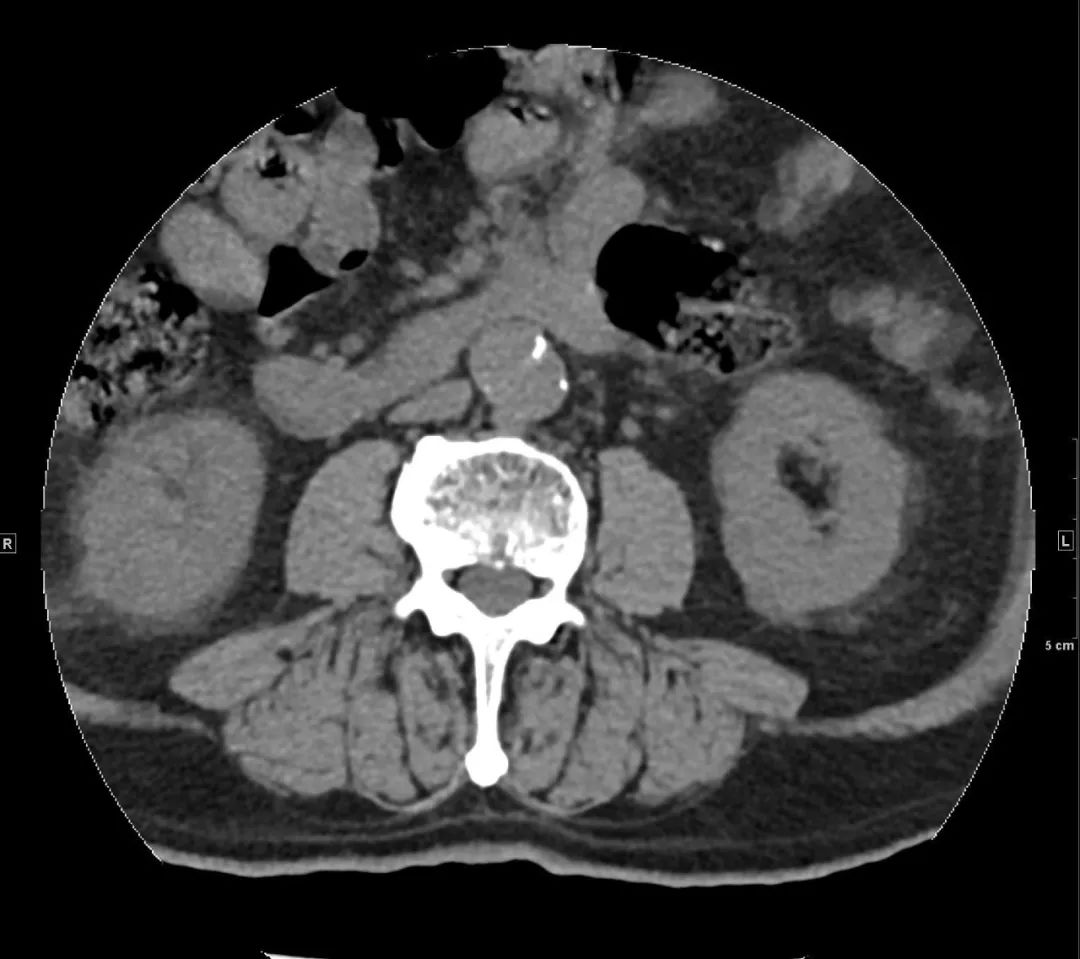

还好,那一下午人不不多,很快开申请单、登记、预约,一小时后做了胸腹盆增强CTA,当看到增强图像时,让我们倒吸一口凉气,约L1椎体水平至左侧髂总动脉夹层。患者紧急住院。

腹主动脉CTA腹腔干水平(骨窗) 左侧髂总动脉(骨窗)